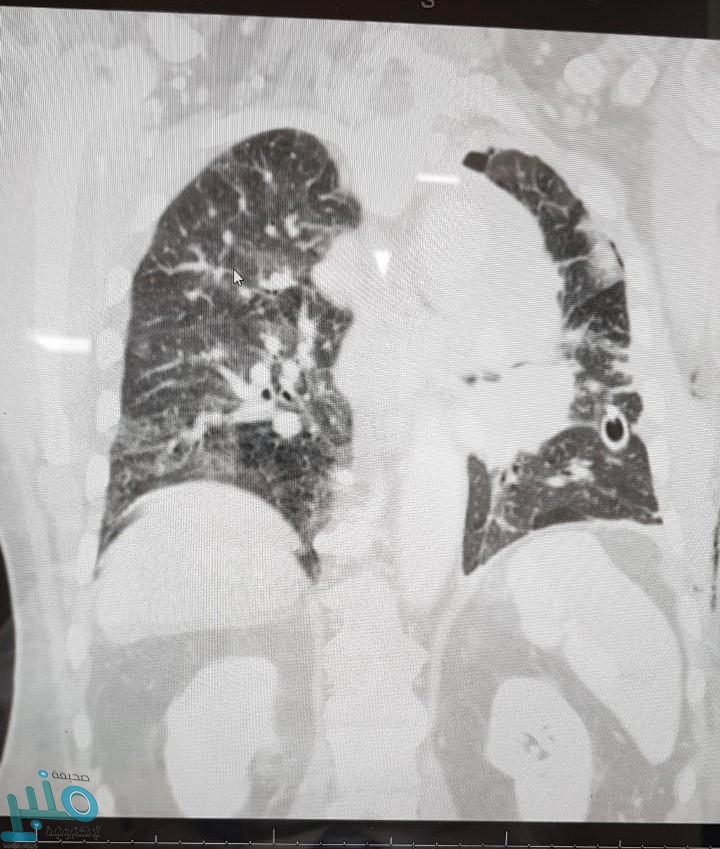

المريض كان يعاني من تجمع مائي مزمن على الرئة اليسرى نتج عنه آلالام شديدة بالصدر والذي تسبب أيضاً بإنكماش تام بالرئة مع ترحيل للفراغ المنصف و وجود ورم على الشريان الأبهر والرئوي الأيسر مع تكتلات في الغدد الليمفاوية إستدعى التدخل الطبي لتحرير الغشاء البلوري وأخذ عينات عن طريق الشق الصدري.

وقد قرر الفريق الطبي المعالج أنه نظراً لعمر المريض 75 عاماً أن الشق الصدري يحمل خطورة عليه وقد تقرر إجراء عمل منظار لجراحة الصدر وبفضل الله تمكن الأطباء من إجراء المنظار بالتعاون مع قسم التخدير بإجراء التخدير عن طريق أنبوبة حنجرية مزدوجة المسار بفصل الرئة اليسرى بالكامل أثناء الجراحة وقد تمت العملية بنجاح.